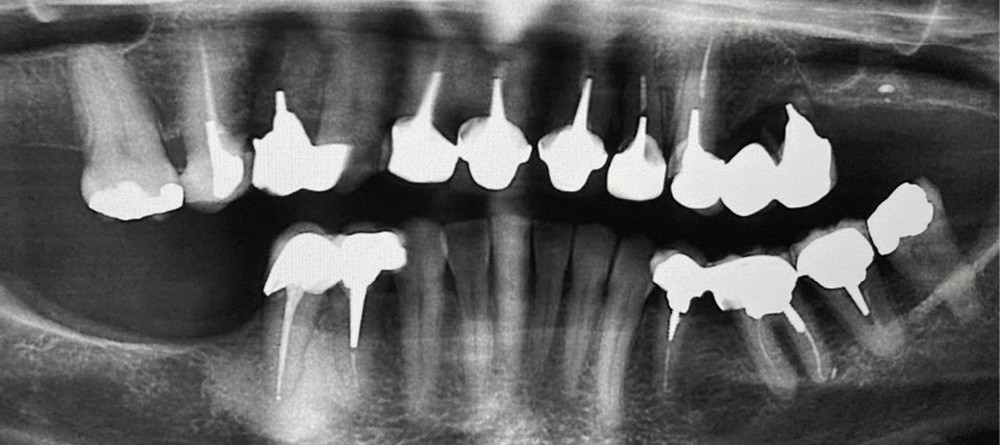

Contexte malin

Un examen clinique attentif prenant en compte les facteurs de risques carieux et parodontaux (contrôle de plaque, tabagisme en particulier) sera réalisé. Un bilan radiographique de première intention sera également nécessaire. A minima, la radio panoramique est indispensable. Elle sera complétée éventuellement par des clichés rétro-alvéolaires. En cas de doute, sur un foyer infectieux chronique péri-apical notamment, ces examens devront être complétés par un bilan d’imagerie tridimensionnel de type scanner ou CBCT. Les lésions de ce type, dans les régions sous-sinusiennes en particulier, sont difficiles d’accès à l’imagerie standard (fig. 1).